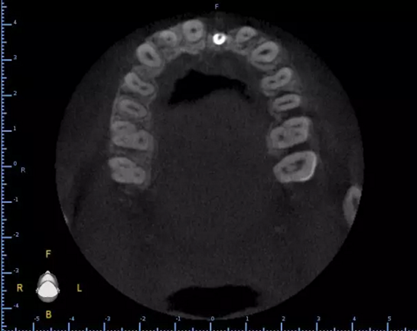

1.術(shù)前CT

術(shù)后CT